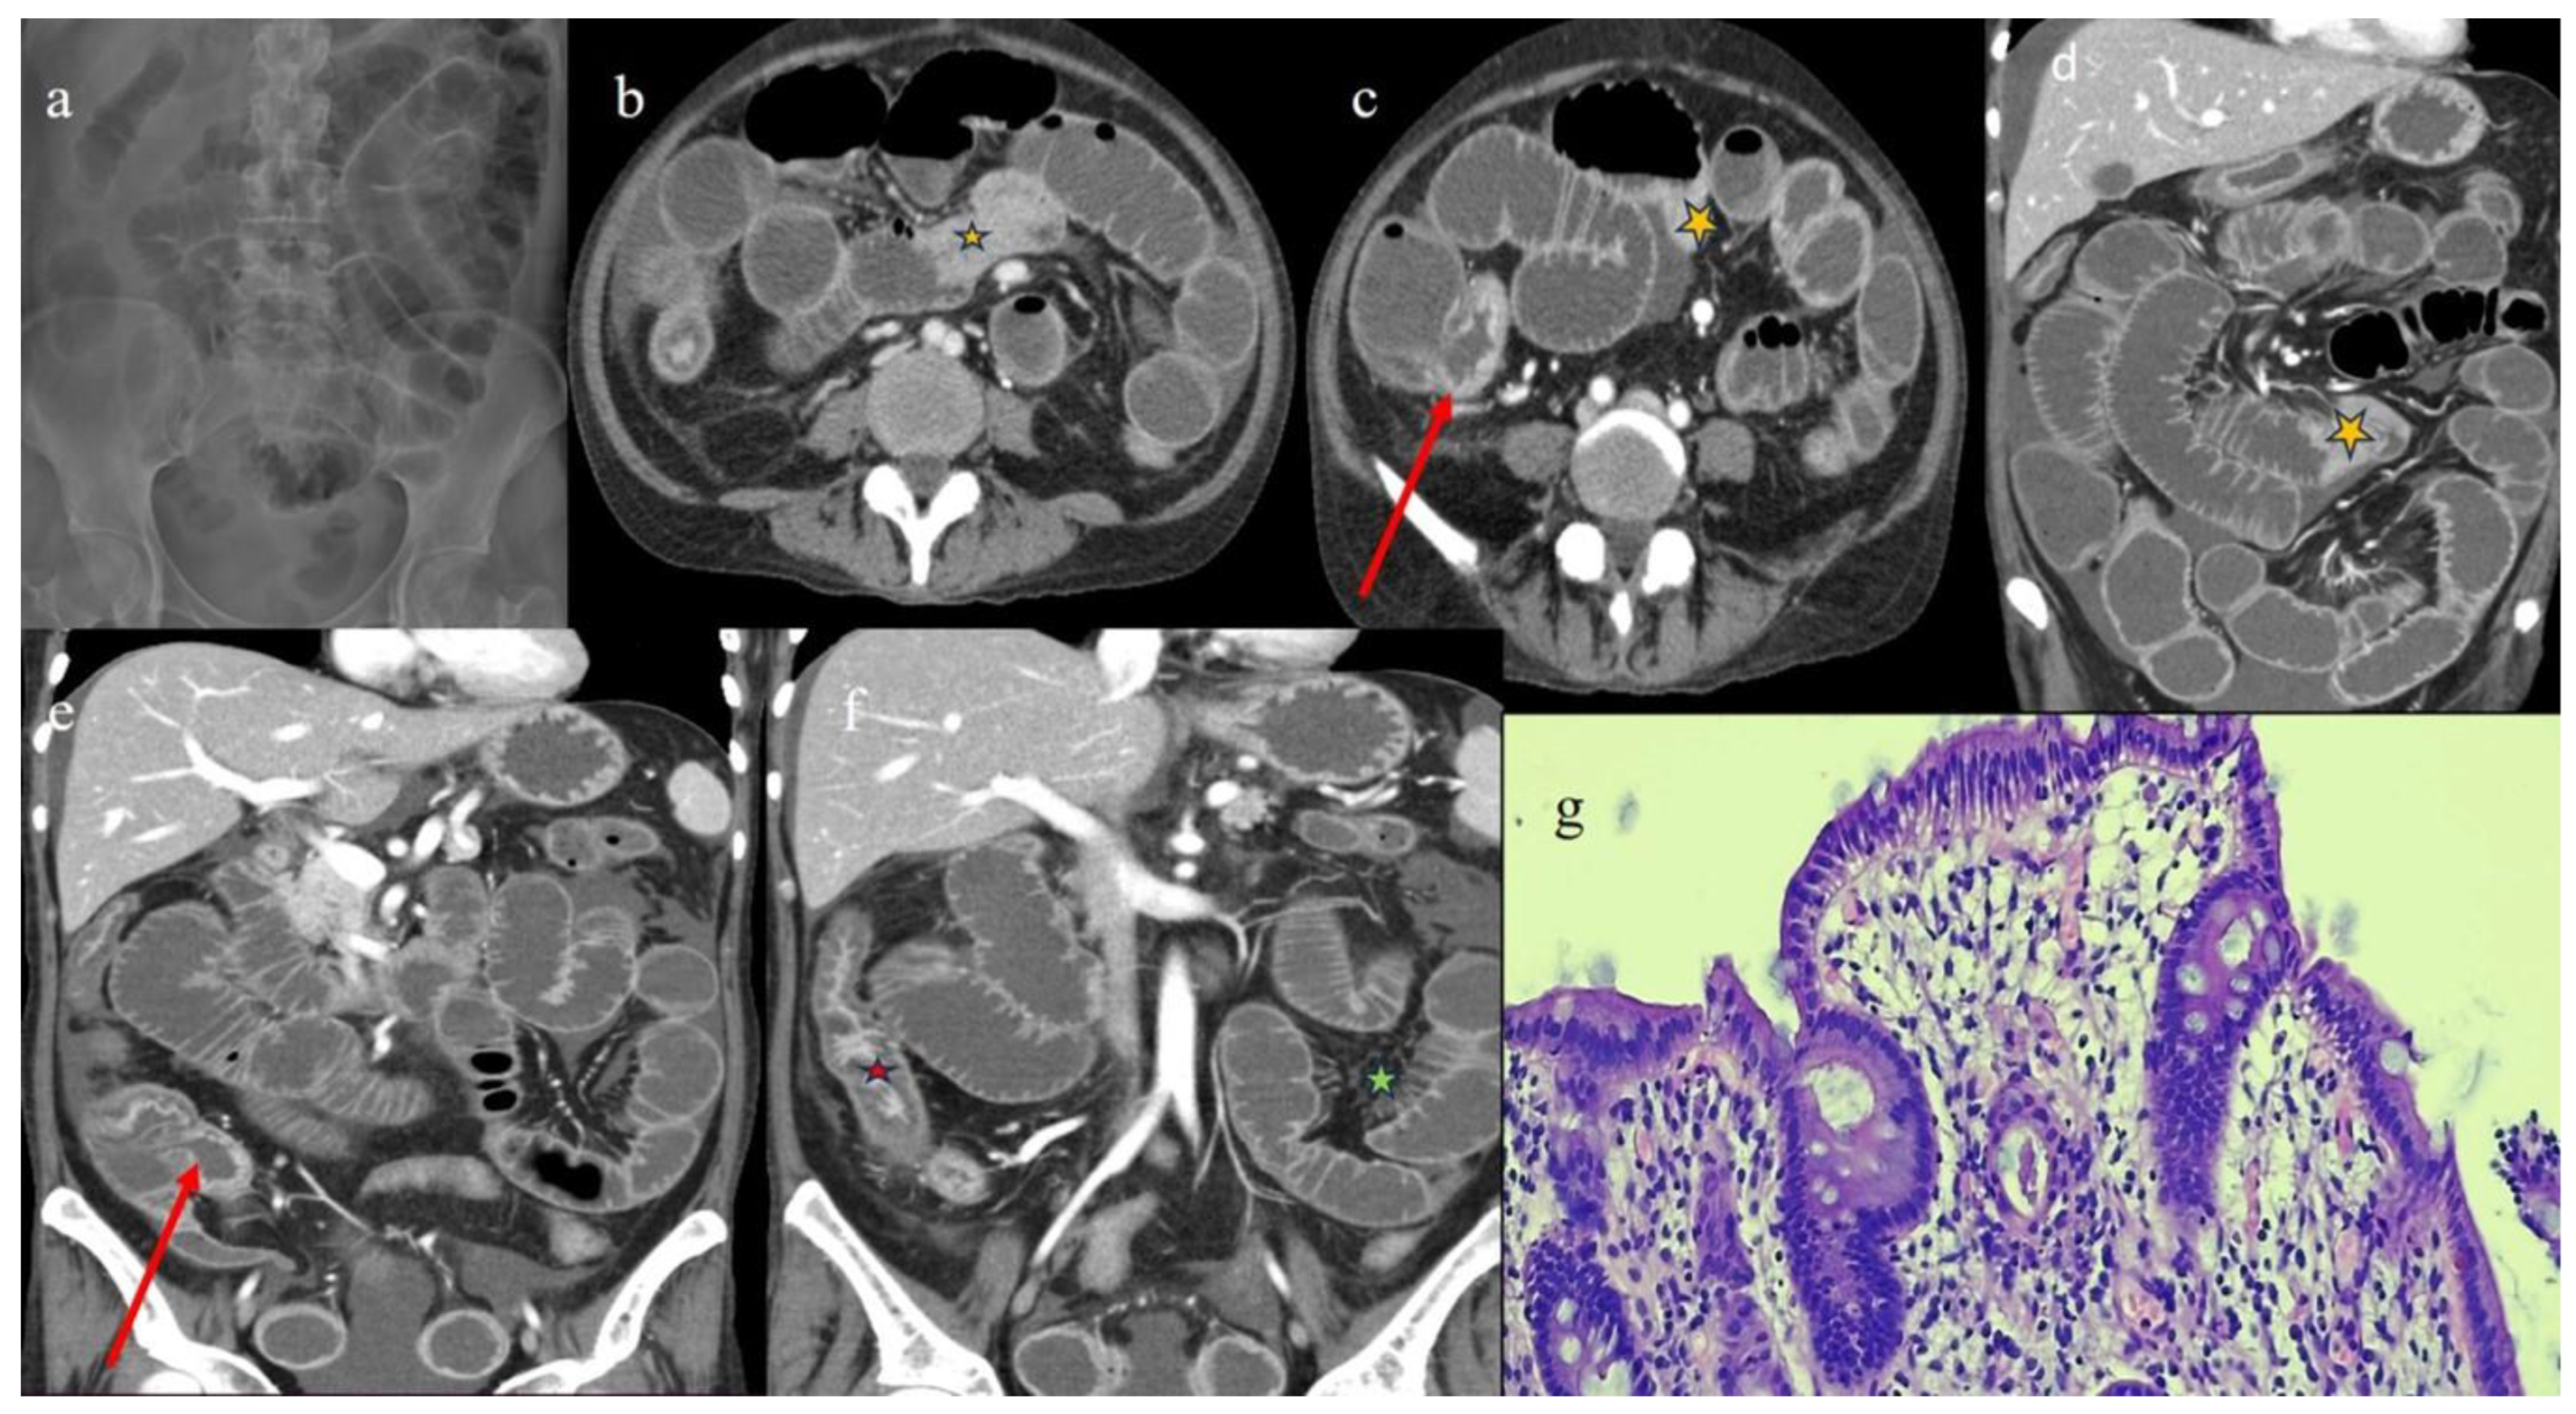

| 5 | 47 | F | ALL PH+ | BM | MUD 10/10 | 9 months | 9 months | AP + SBO | co | III | D |

| 5 | P | P | Multisegmental thickness with stenosis on jejunal loops and SBO and segmental and focal thickness on the terminal ileus and appendix | Diffuse parietal thickness with stratified enhancement | Mild comb sign, poor reactive mesenteric lymph node, small air bubbles in the ascites | Small splenic areas of ischemia |